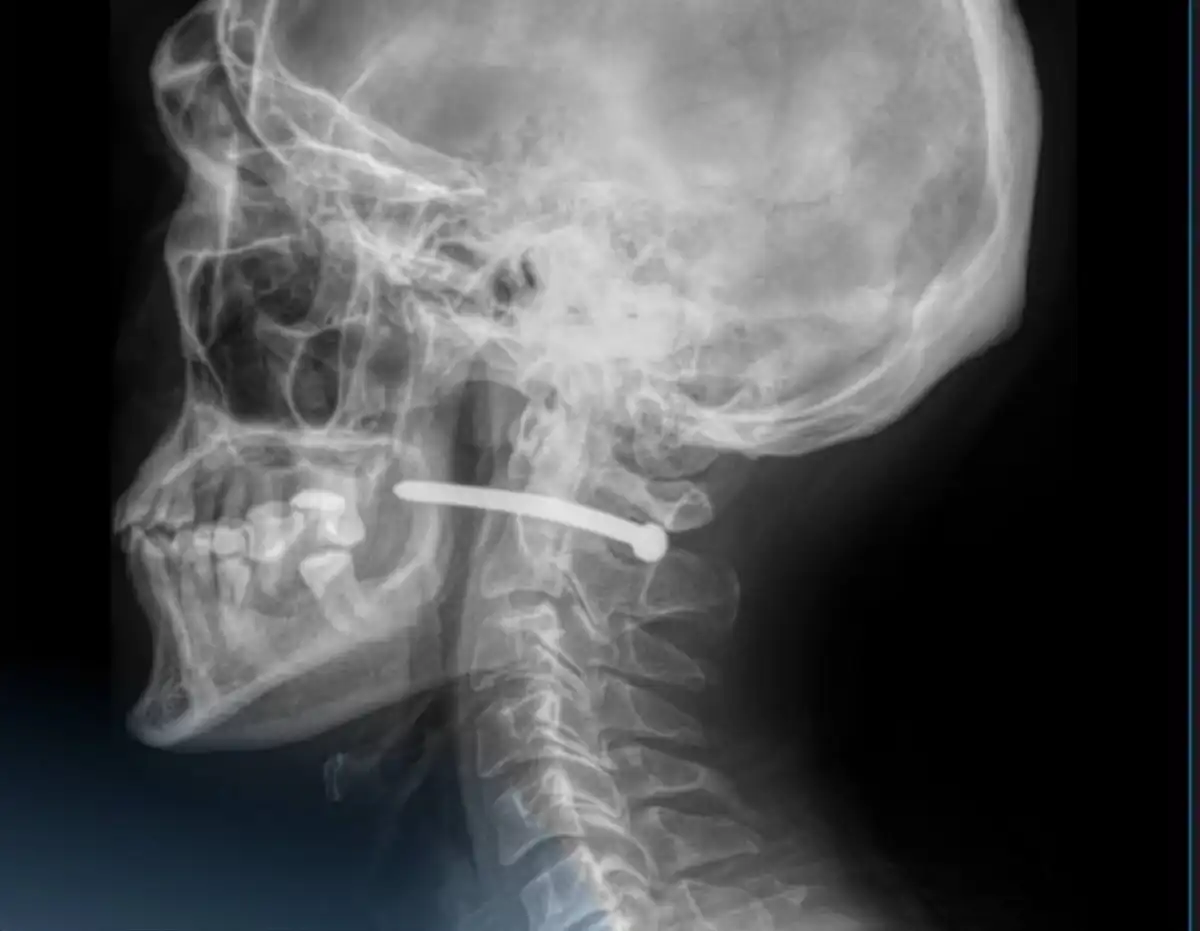

Жөндеу кезінде ер адамның мойынына шеге кіріп кеткен

Петропавл қаласында 51 жастағы ер адам жөндеу жұмысы кезінде ауыр жарақат алды. Пневмопистолеттен оқыс оқиға кезінде шеге ұшып, ер адамның мойнына қадалған.

фото: Әлеуметтік желіден

Дәрігер-хирургтар мойнындағы темір шегені алып шыққан. Мамандардың айтуынша, ер адам нағыз сәттілікпен аман қалған, себебі шеге өмірлік маңызды тамырлардың жанынан өтіп, кеңірдек пен омыртқаға тимеген.